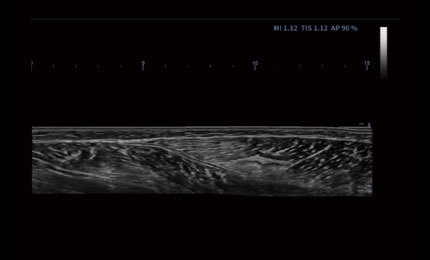

Panorama

Rozszerzone pole widzenia wyświetla więcej informacji obrazowych bez utraty jakości obrazu. Jest wygodnym podejściem do dużych organów, zwłaszcza struktur układu mięśniowo-szkieletowego. Posiada wskazania dotyczące kierunku i prędkości skanowania.